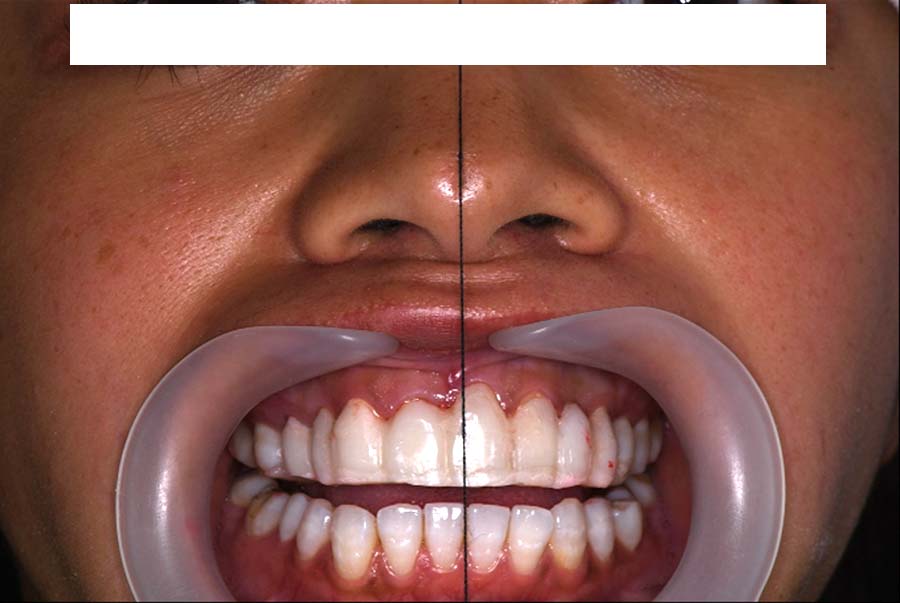

バイトアップ後

顔貌の変化

2024年 3月 初診時

2024年 10月10日

2025年 12月25日